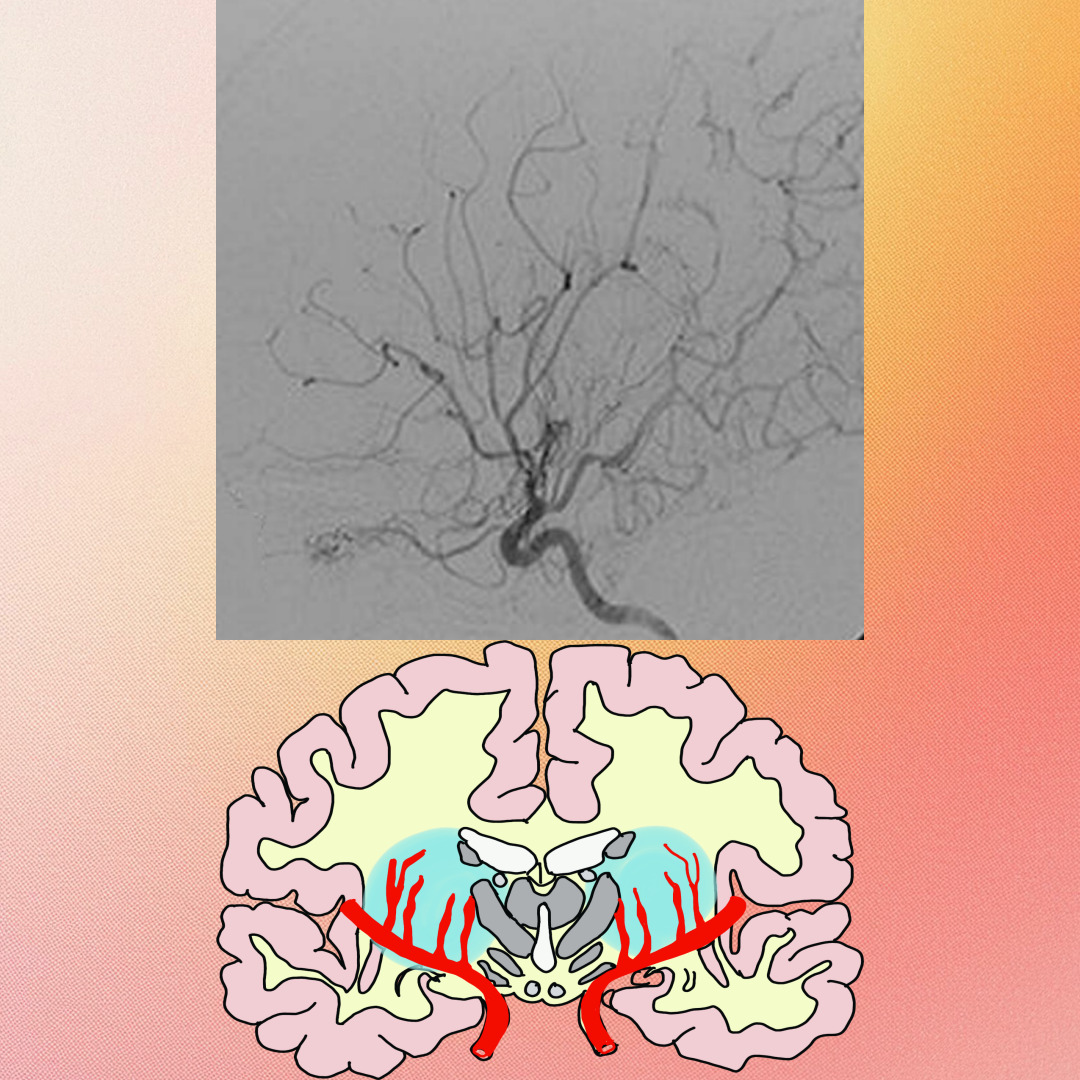

모야모야병은 특별한 이유 없이 뇌에 혈액을 공급하는 뇌 속 동맥혈관 말단부위가 서서히 좁아지다가 결국 막히는 질환입니다 이렇게 되면 뇌혈류가 부족해지면서 허혈성 증상이 나타나거나 부족한 혈류량을 보전하기 위해 생겨난 혈관의 파열로 출혈성 뇌졸중이 발생하는 질환입니다

희귀 질환인 모야모야병은 확실한 원인이 밝혀지지 않아 모야모야병 자체를 치료할 수 있는 방법이 없습니다 때문에 보존적인 약물 치료와 수술 치료가 시행되고 있으며 수술 치료는 직접 혈관과 혈관을 연결하여 혈류량을 늘리는 직접 혈관 문합술 다른 부분의 혈관이 자라나서 시간이 걸리지만 보조적으로 혈류량을 늘리는 간접 혈관 문합술 그리고 두 수술을 동시에 시행하는 병합 혈관 문합술 세 종류가 있습니다.

소아의 경우 두 수술법 모두 효과적으로 알려져 있으며 성인은 간접 혈관 문합술은 효과자 적어서 주로 직접 혈관 문합술을 시행합니다.